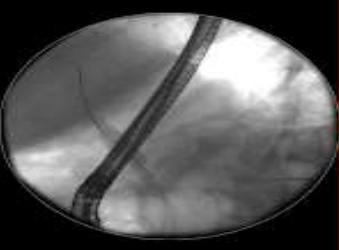

Patient was treated for suspected AIH with trial of prednisolone 30mg once daily for 1 week with minimal improvement. She then developed another episode of ascending cholangitis. Given the minimal response with clinical deterioration, Prednisolone was stopped. Repeat ultrasound showed cholecystitis, liver cirrhosis, dilated CBD 9.7mm and intrahepatic duct with gallstones. Further ERCP revealed dilated and clear CBD without gallstones, abnormal hepatic ducts and thready intrahepatic ducts suggestive of primary sclerosing cholangitis (PSC). CBD stent was removed. She was then treated with ursodeoxycholic acid and rotatory antibiotics including oral 2-week Co-amoxiclav followed by 2-week Ciprofloxacin.

Image 2: thready intrahepatic ducts demonstrated during ERCP stent insertion